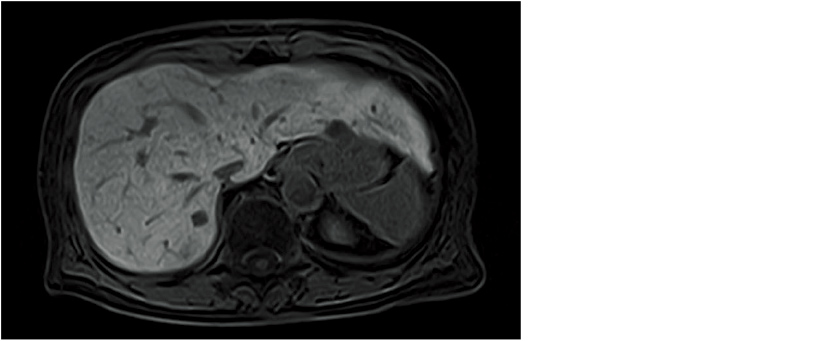

Abdominal dynamic image (TIGRE)

This function can map the distribution of T2* values to improve the visibility of iron deposition in liver tissue. A special sequence based on the GRE method (ADAGE) is available to acquire MultiEcho images used to automatically calculate T2* values. When analysis is conducted on the console, a color map of these T2* values is superimposed on a morphological image to create a T2* RelaxMap.

You can also create an R2 (Relaxation rate) map based on 1/T2* values. The relative color display of an area with shortened T2* values can be used as a quantitative evaluation of iron deposits.